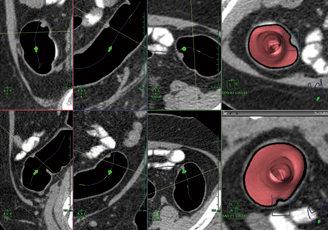

3. 直交カット断面にて解析を行う(図5)。このとき,仮想内視鏡画面を正面からカットし,オブリーク断面とほぼ同じ大きさの断面で処理を行う。また,大腸の断面の観察により,隆起病変とタギングされた残液の区別ができるため,クレンジング処理はOFFにする。観察中は仮想内視鏡画面,オブリーク断面,直交カット断面を同時に確認しながら,隆起があれば,“ポリープ確認”で抽出して観察し,CT値や大きさ,肛門からの距離などを記録保存する。このときの隆起病変のCT値は,約10〜80HUとしており,内部構造の均一性も重要である。次に,詳細読影(図6)に切り替え,アキシャル断面にて時計方向のどの位置にあるか記録する。

4. 比較表示にて確認した隆起について比較していく(図7)。

図5 直交カット断面 仮想内視鏡画面,オブリーク断面,直交カット断面の3種類同時観察で解析が行いやすい。

図5 直交カット断面

仮想内視鏡画面,オブリーク断面,直交カット断面の

3種類同時観察で解析が行いやすい。

図7 比較表示による隆起観察 最後に比較表示で隆起部位の確認を行う。

図7 比較表示による隆起観察

最後に比較表示で隆起部位の確認を行う。